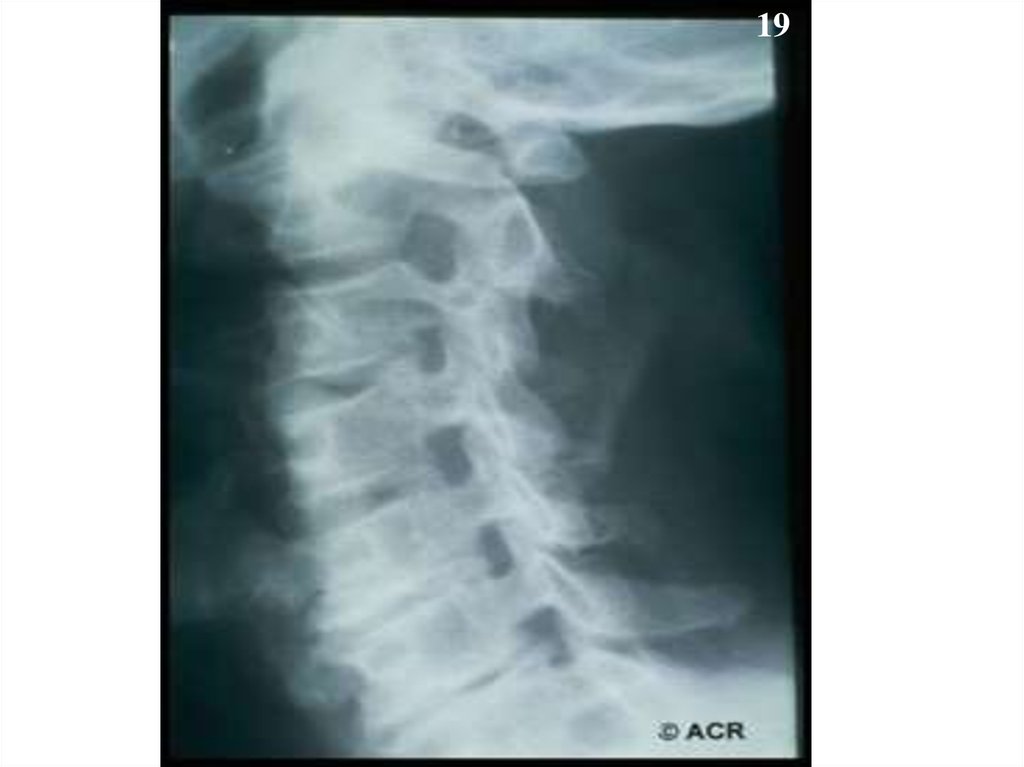

19.

19